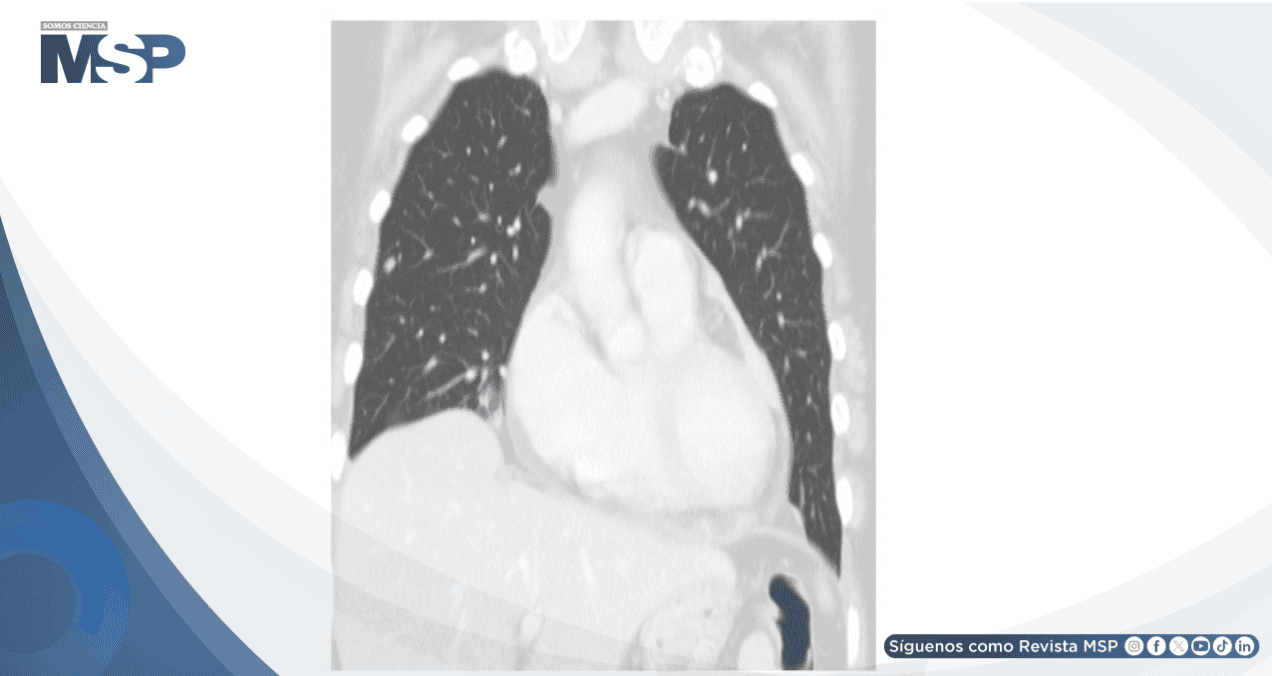

La tomografía computarizada toraco-abdomino-pélvica posterior reveló derrame pleural bilateral con atelectasia parenquimatosa adyacente, derrame pericárdico residual leve y, de manera significativa, engrosamiento pericárdico en el lado izquierdo sugestivo de implantes metastásicos tras la administración de contraste intravenoso. Adicionalmente, se identificaron múltiples nódulos en todos los lóbulos pulmonares compatibles con metástasis.